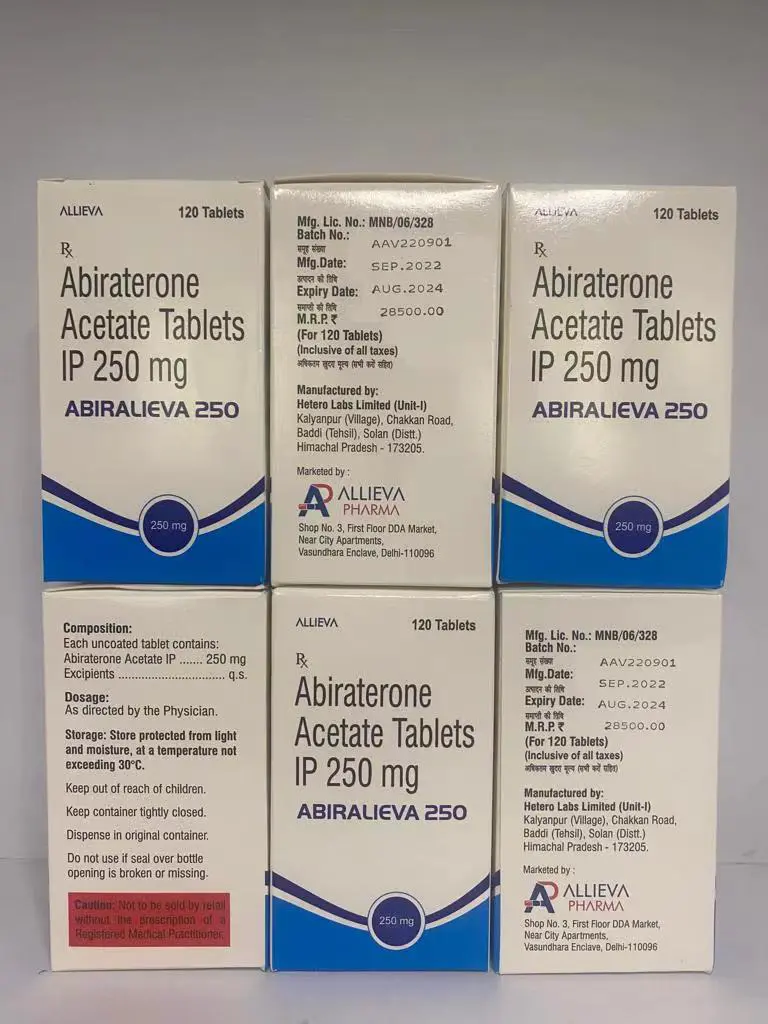

泽珂 Abiralieva 阿比特龙 Abiraterone

Xbira(阿比特龙)的作用是减少体内雄激素的产生。雄激素是可以促进前列腺癌生长的雄性激素。Xbira与类固醇药物(泼尼松或甲基强的松龙)一起用于治疗已扩散到身体其他部位的前列腺癌。Xbira用于无法通过手术或其他药物治疗的前列腺癌男性。